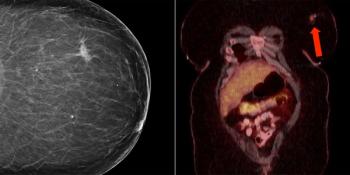

A 41-year-old woman with a past medical history notable for HIV underwent her first screening mammogram, which demonstrated a 1.5-cm irregular focal asymmetry in the left breast. What is your diagnosis?